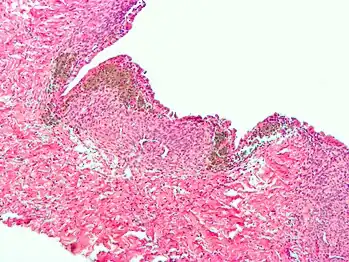

Histopathology

For a histopathological diagnosis, at least two of the following three criteria should be present:[88]

- Endometrial type stroma

- Endometrial epithelium with glands

- Evidence of chronic hemorrhage, mainly hemosiderin deposits

Immunohistochemistry has been found to be useful in diagnosing endometriosis as stromal cells have a peculiar surface antigen, CD10, thus allowing the pathologist go straight to a staining area and hence confirm the presence of stromal cells and sometimes glandular tissue is thus identified that was missed on routine H&E staining.[89]

Micrograph of the wall of an endometrioma. All features of endometriosis are present (endometrial glands, endometrial stroma and hemosiderin-laden macrophages).